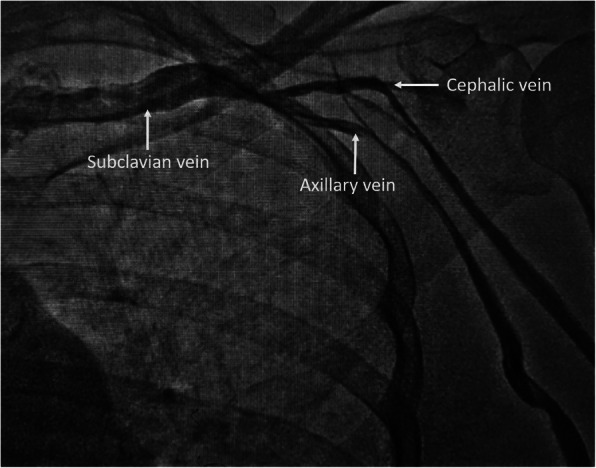

A temporary pacemaker was inserted through the right femoral venous route and she was subsequently planned for permanent single-chamber pacemaker implantation. A Dual-chamber pacemaker, although ideal, was refused by the patient due to financial reasons. As part of the hospital protocol, an intravenous contrast (iohexol; 5 ml diluted in 5 ml normal saline) injection was given through the left brachial vein to delineate the venous anatomy and drainage of left upper limb veins, which showed good-sized axillary and subclavian veins draining into the left brachiocephalic vein and then into superior vena cava (Fig. 1). We made the skin incision in the left infraclavicular fossa and prepared the subcutaneous pocket for device placement. Then, we proceeded to an axillary venous puncture with 16 G needle using the Seldinger technique. However, the axillary vein could not be cannulated despite multiple attempts. To find out the cause, we gave another contrast injection in the left brachial vein which revealed severe spasm of axillary and subclavian veins (Fig. 2). Then, axillary vein puncture was attempted after 15 min of giving two sequential boluses of intravenous nitroglycerin (200 mcg followed by 400 mcg) with a gap of 5 min, still, the axillary vein could not be cannulated. A venogram was not done on the right side to avoid the risk of venous spasm and the axillary vein was cannulated using anatomical landmarks, and the pacemaker was successfully implanted in the right infraclavicular pocket (Fig. 3). Active fixation lead was screwed in right ventricular septum and the device was placed in a right infraclavicular pocket; the VVIR mode for pacing was selected. Skin incisions on both sides of the chest were closed in layers.

Fig. 1.

Intravenous contrast injection from the left brachial vein showing good-sized axillary and subclavian veins